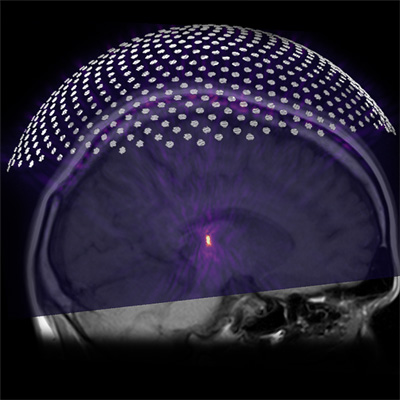

Catherine Phillips, MD, has joined Vanderbilt University Medical Center from Harvard Medical School’s Brigham and Women’s Hospital in Boston. She began seeing patients in July.

“We are thrilled to recruit Dr. Phillips back to Vanderbilt from her role as chief of Ultrasound at Brigham and Women’s Hospital,” said Reed Omary, MD, MS, Carol D. and Henry P. Pendergrass Professor and chair of Radiology and Radiological Sciences. “She is one of the nation’s premiere experts in diagnostic ultrasound imaging and ultrasound-guided procedures, especially for obstetric indications. Dr. Phillips is also a natural collaborator who excels at serving the needs of our patients and busy referring physicians.”

She joins the Department of Radiology as an assistant professor with primary clinical interests including first trimester and abdominal ultrasounds and infertility. Her professional interests include mentoring and leadership development.